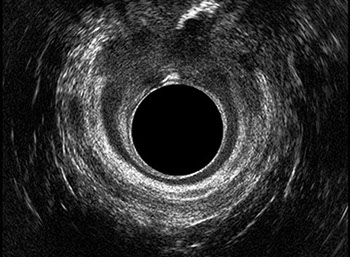

L’ecografia transanale è un esame diagnostico per immagini che consiste nell’introduzione di un trasduttore ad ultrasuoni. Le immagini qualitativamente migliori del canale anale sono ottenute usando un trasduttore rotante, montato in un manipolo rigido, che fornisce un’immagine a 360°. Con le apparecchiature più moderne è anche possibile ottenere immagini tridimensionali.

L’ecografia transanale permette di distinguere la sottomucosa che riveste il canale anale, lo sfintere anale interno, e lo sfintere anale esterno.